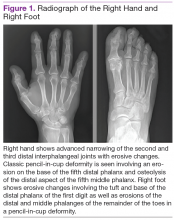

Radiographic data, such as X-rays of the hands and feet, can confirm the clinical distribution of joint involvement and show evidence of erosive changes. Further destructive changes include osteolysis (bone resorption) that may cause the classic pencil-in-cup deformity, typically seen in arthritis mutilans (Figure 1). 3 Other radiographic evidence of PsA can include proliferative changes with new bone formation seen along the shaft of the metacarpal and metatarsal bones. 3 Patients with axial involvement can have evidence of asymmetric sacroiliitis, which can be seen on radiographs. Asymmetric syndesmophytes, or bony outgrowths, can also be seen throughout the axial spine. 3